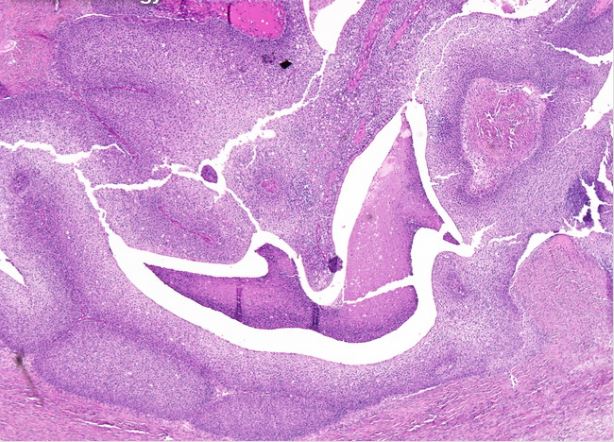

We consider two binary histopathology classification tasks, both framed as “cancer” vs. “non cancer”. The first dataset is the Ovarian Cancer & Subtypes Histopathology dataset111https://www.kaggle.com/datasets/bitsnpieces/ovarian-cancer-and-subtypes-dataset-histopathology, which contains digital pathology patches extracted from hematoxylin and eosin (H&E) stained ovarian tissue slides. We group the available subtypes into a single positive class (ovarian cancer) and use benign or non tumoral tissue as the negative class.

The second dataset is a subset of the LC25000 dataset222https://www.kaggle.com/andrewmvd/lung-and-colon-cancer-histopathological-images, which contains colon histopathology images with normal and tumoral samples. We select only colon images and map them to a binary label (cancer vs. non cancer). Representative examples of ovarian and colon patches for both classes (Figure 2).

| (a) Ovarian cancer | ||

| (b) Ovarian normal | ||

| (c) Colon cancer | ||

| (d) Colon normal | ||